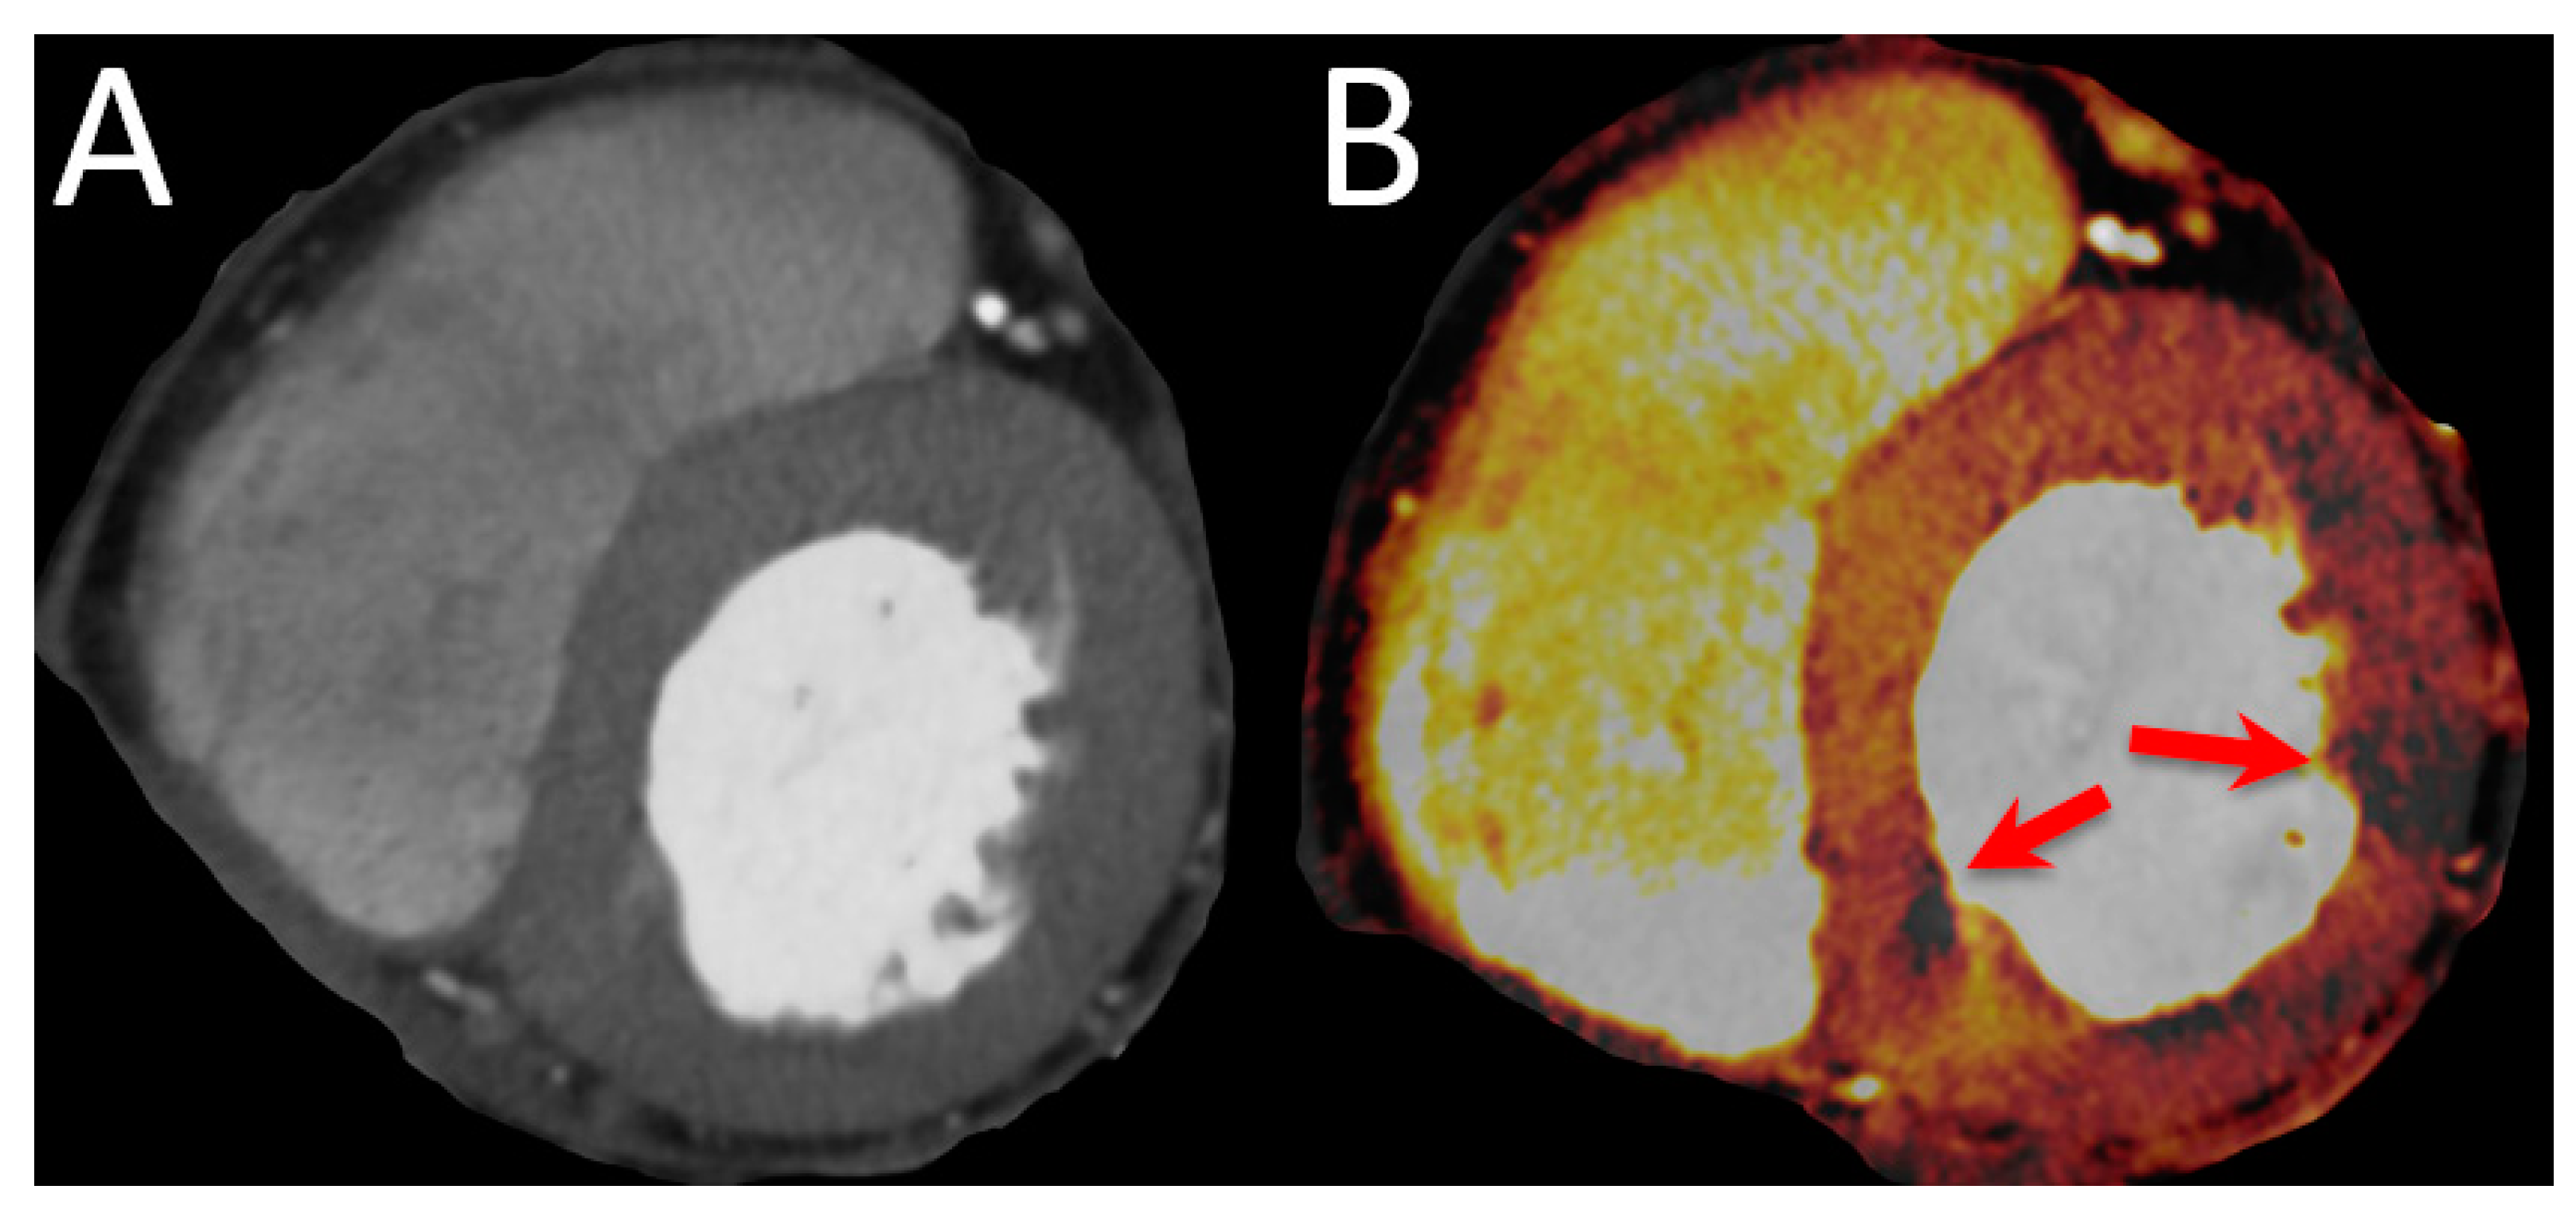

Figure 4. Imaging example of a CTP. A 78-year-old female patient with atypical angina and intermediate pretest probability. (A) shows the multiplanar reconstructions of the basal short axis with a DECT at 90 kV and 150 kV. (B) shows the perfused blood volume which is reduced in two segments (red arrows).